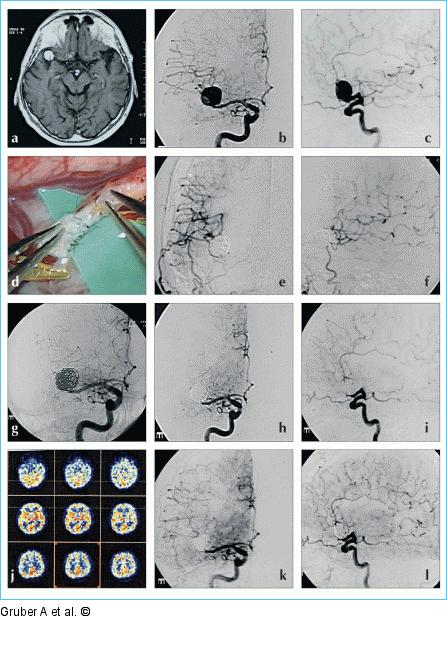

Abbildung 11a-l: Kombinierte Therapie Kombinierte Therapie von komplexem breitbasigem Mediabifurkationsaneurysma (a–c) durch endovaskulären Gefäßverschluß unter Bypaßschutz. Zwei Tage nach einer vorbereitenden Externa-Interna-Doppelanastomose (d–f) zur Kollateralversorgung des rechtshirnigen Mediastromgebietes wird das Mediaaneurysma unter Verschluß der Bifurkation mit absetzbaren Platin-Coils embolisiert (PAO) (g–i). Spätere HMPAO-SPECT-Untersuchungen (j) demonstrieren gute Kollateralversorgung der rechten Hemisphäre über die Doppelanastomose. Kontrollangiogramme veranschaulichen die postinterventionellen Durchblutungsverhältnisse der rechten Hemisphäre (k–l). Bei Füllung der A. carotis communis rechts stellen sich über die A. carotis interna orthograd perfundiert die rechte Anteriorgruppe sowie der rechte Mediahauptstamm mit den striolentikulär perforierenden Ästen bis zum Ort des Gefäßverschlusses dar. Über die Bypässe füllt sich das rechtshirnige Mediaterritorium distal des Gefäßverschlusses retrograd. Das Aneurysma ist verschlossen. |

Kombinierte Therapie von komplexem breitbasigem Mediabifurkationsaneurysma (a–c) durch endovaskulären Gefäßverschluß unter Bypaßschutz. Zwei Tage nach einer vorbereitenden Externa-Interna-Doppelanastomose (d–f) zur Kollateralversorgung des rechtshirnigen Mediastromgebietes wird das Mediaaneurysma unter Verschluß der Bifurkation mit absetzbaren Platin-Coils embolisiert (PAO) (g–i). Spätere HMPAO-SPECT-Untersuchungen (j) demonstrieren gute Kollateralversorgung der rechten Hemisphäre über die Doppelanastomose. Kontrollangiogramme veranschaulichen die postinterventionellen Durchblutungsverhältnisse der rechten Hemisphäre (k–l). Bei Füllung der A. carotis communis rechts stellen sich über die A. carotis interna orthograd perfundiert die rechte Anteriorgruppe sowie der rechte Mediahauptstamm mit den striolentikulär perforierenden Ästen bis zum Ort des Gefäßverschlusses dar. Über die Bypässe füllt sich das rechtshirnige Mediaterritorium distal des Gefäßverschlusses retrograd. Das Aneurysma ist verschlossen. |